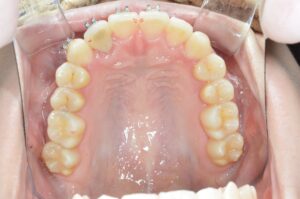

2回目の追加治療計画

細かい私のために、院長が一生懸命練ってくださった治療計画は全11ステージです。

上の前歯には今までで一番大きなアタッチメントがドーンと付きます。

最終的には、こんな歯並びになる予定です。

何が変わったのか分かりづらいので、こちらもご覧ください!